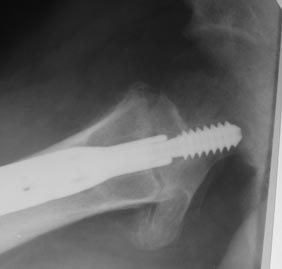

Уважаемые коллеги! Нужен совет. Появился такой больной Х., 23 года.

Травма 26.11.2013г. оступился в снегу, получил закрытый межвертельный

перелом левого бедра. Оперирован  09.12.2013г. Последние две недели

ходил с тростью, занимался ЛФК. Движения в левом тазобедренном суставе

безболезненные, незначительно ограничены.  Три  дня назад появились

ноющие боли в нижней трети левого бедра , субфебрилитет после физнагрузки.

Из обследования, пока, сделанные сейчас снимки.

Д-з: миграция конструкции, АНГБК?

Наши рекомендации:

1. Ходьба на костылях, не наступая на левую ногу.

2. Для уточнения консолидации перелома и степени аваскулярных нарушений КТ.

3. По результатам–  удаление фиксатора, костная пластика по каналу от

винта либо

остеотомия?